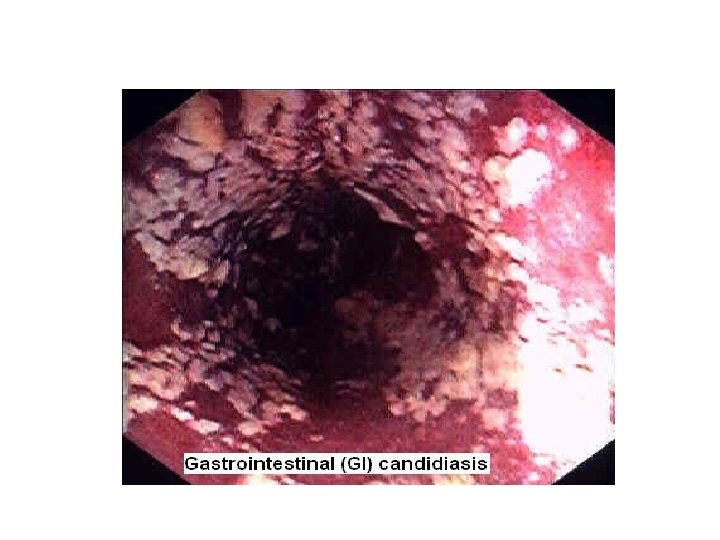

Candida és egyéb gombás betegségek